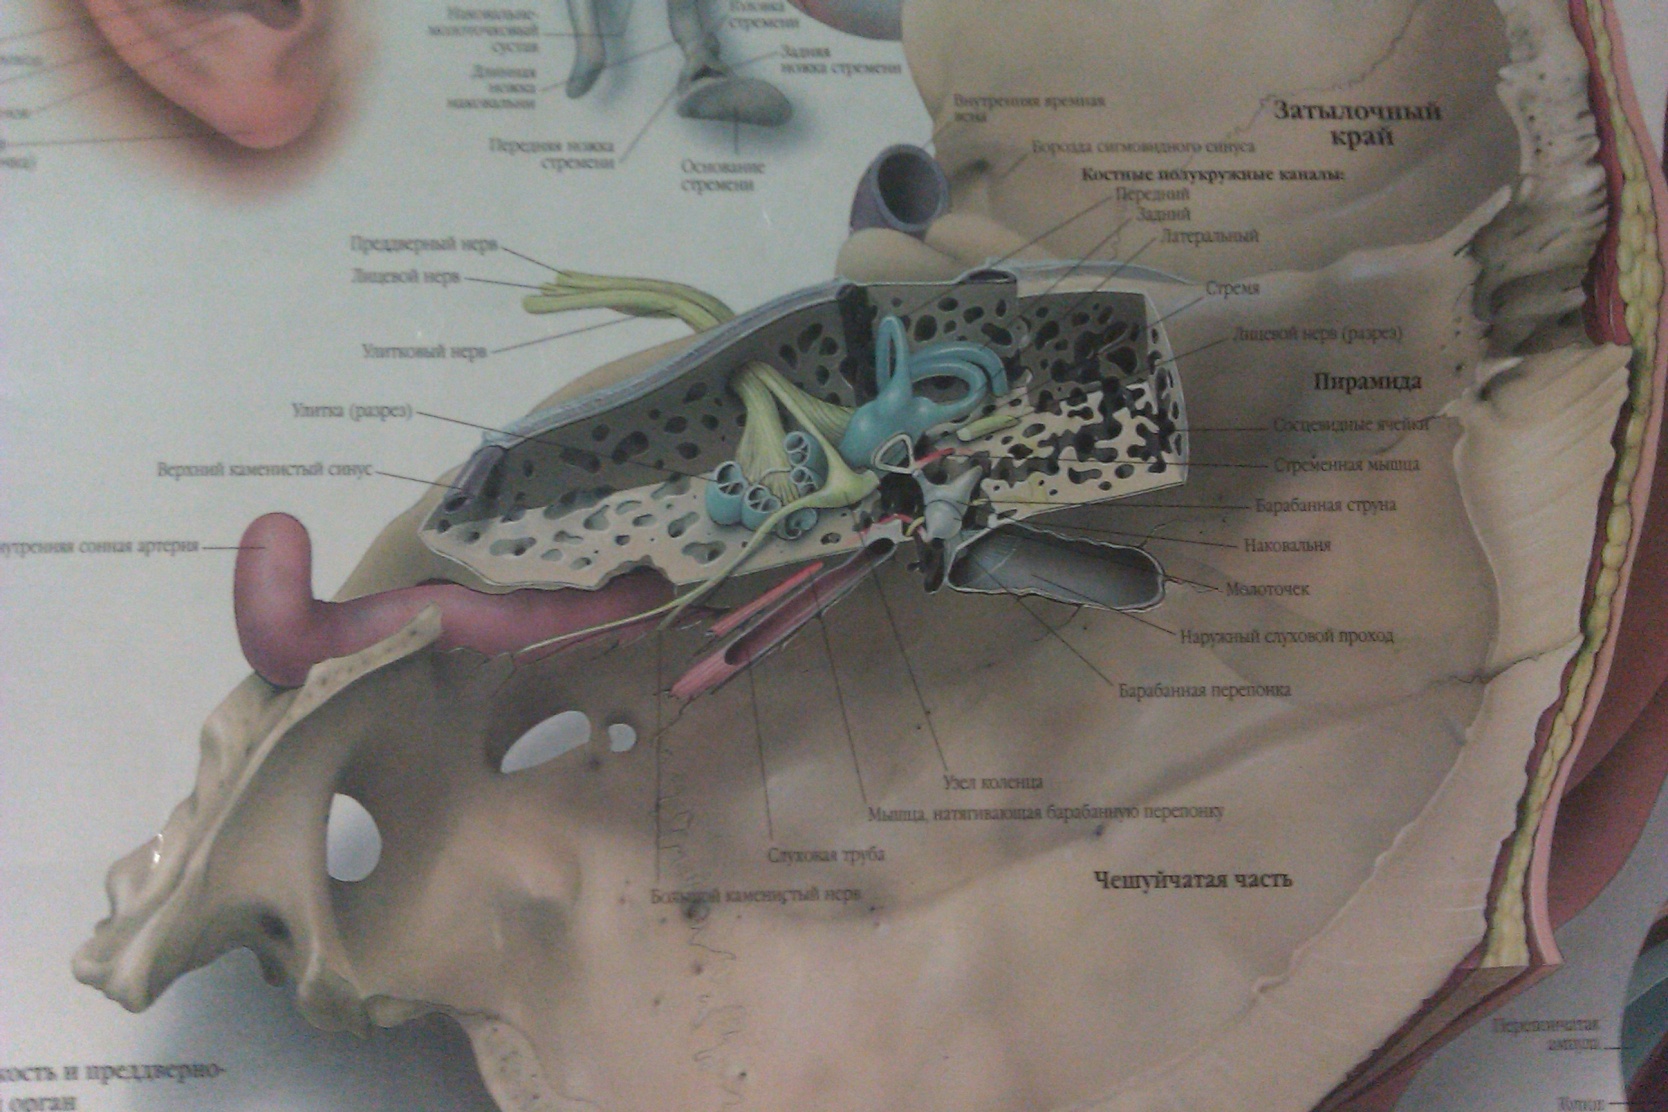

КТ анатомия сосцевидного отростка: особенности и показания